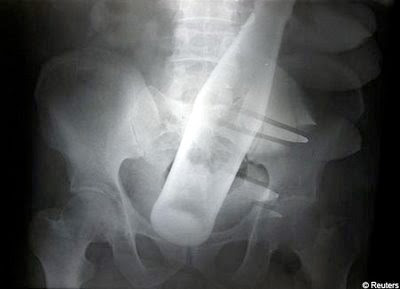

O sticlă în fundul unui bătrân de 60 de ani, căruia i-au îndesat-o acolo nişte hoţi.